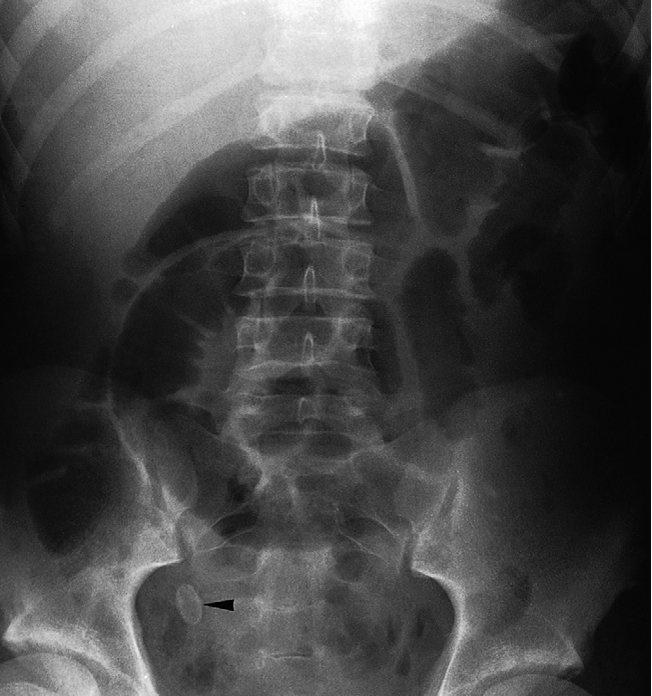

Calcified faecoliths may be seen in diverticula of the colon or in the appendix. The presence of an appendicolith is a strong indication that the patient has acute appendicitis Appendicolith The oval calcified shadow (arrowhead) is a faecolith in the appendix. Note the dilated loops of small bowel in the centre of the abdomen due to peritonitis – the so-called sentinel loops.